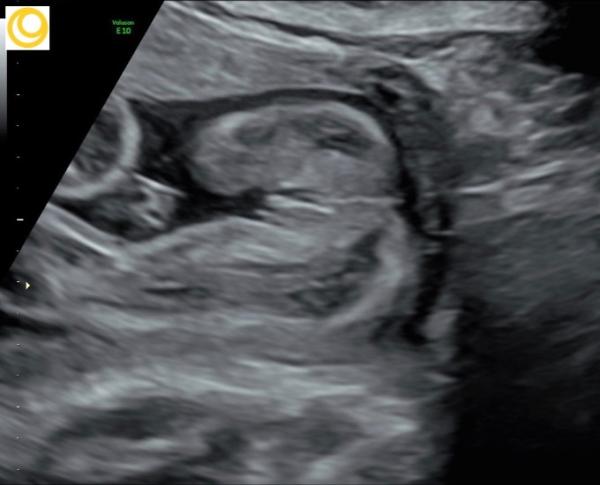

Huhu Ich hab ja ein Outing zum Mädchen bekommen , kann es aber irgendwie noch nicht ganz glauben Könnt ihr Vilt mal eure Outing- Bilder von euern Mädels zeigen ? Bin so neugierig Lg

Bild zu Mädchen outing Bilder - Forum für April - Mamis